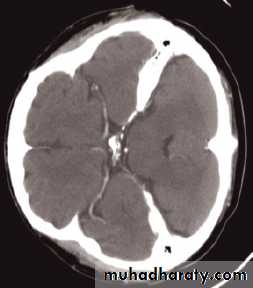

Mass effect

• The lateral ventricles should be examined to see if they are displaced or compressed.• Shift of midline structures, such as the septum pellucidum , the third ventricle, or the pineal, is a common finding with intracranial masses.

Enlargement of ventricles

There are two basic mechanisms which cause the cerebral ventricles to enlarge:• Obstruction to the CSF pathway, either within the ventricular system (non-communicating hydrocephalus) or over the surface of the brain (communicating hydrocephalus)

• Secondary to atrophy of brain tissue